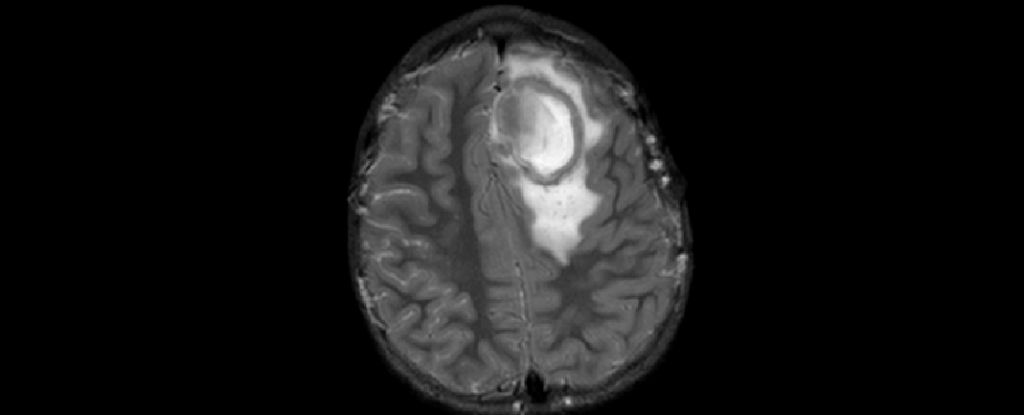

Cases of brain abscesses in American children have surged to new heights following the easing of pandemic restrictions, according to reports from the CDC. These abscesses, which are relatively rare but dangerous, are typically caused by bacteria or fungi entering the brain through respiratory infections such as COVID-19, the flu, or sinusitis. The CDC emphasizes the importance of children staying up-to-date with their vaccinations to prevent these infections. While cases have fallen since a peak in December 2022, they remain above the baseline maximum, indicating the need for continued monitoring and vigilance.